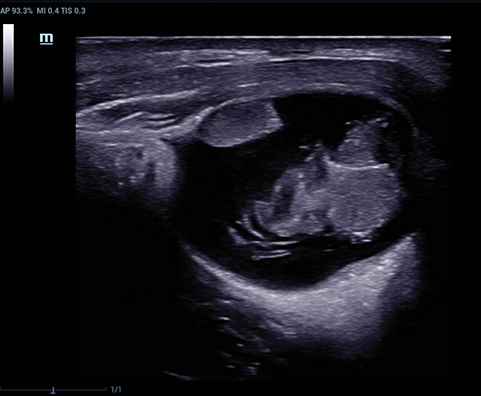

Перфузия яичника

Фолликулы